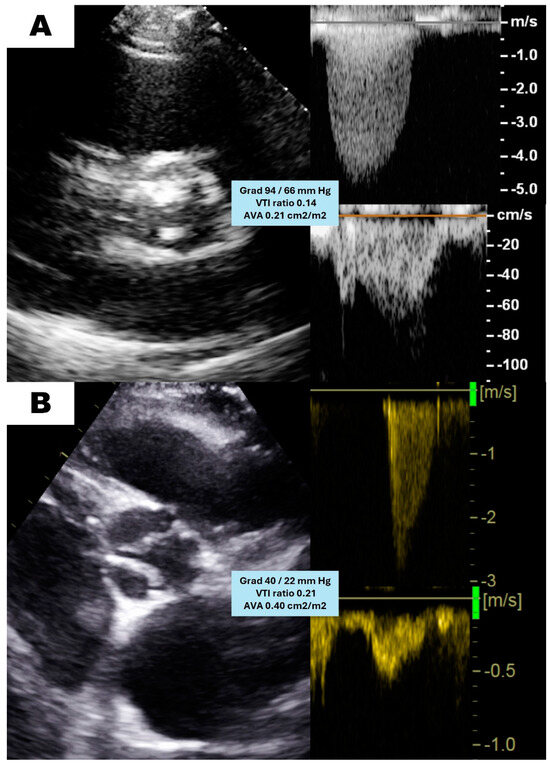

| Maximum velocity (m/s) | 4.3 ± 0.6 | 4.5 ± 0.4 | 3.4 ± 0.4 | <0.001 |

| Mean gradient (mm Hg) | 45 ± 13.3 | 49.3 ± 10.8 | 27.5 ± 6 | <0.001 |

| Aortic VTI (cm) | 99.2 ± 20.2 | 105.1 ± 16.9 | 75.3 ± 14.1 | <0.001 |

| LVOT VTI (cm) | 21.9 ± 8 | 22.9 ± 8.4 | 17.7 ± 4.2 | <0.001 |

| VTI ratio | 0.22 ± 0.06 | 0.22 ± 0.06 | 0.24 ± 0.05 | 0.04 |

| AVA (cm2) | 0.67 ± 0.17 | 0.66 ± 0.18 | 0.71 ± 0.13 | 0.048 |

| SV index (mL/m2) | 37.4 ± 10.5 | 39.6 ± 10.3 | 28.5 ± 4.8 | <0.001 |

| LVEF (%) | 62.3 ± 9.2 | 62 ± 9.7 | 63.6 ± 7.2 | 0.379 |